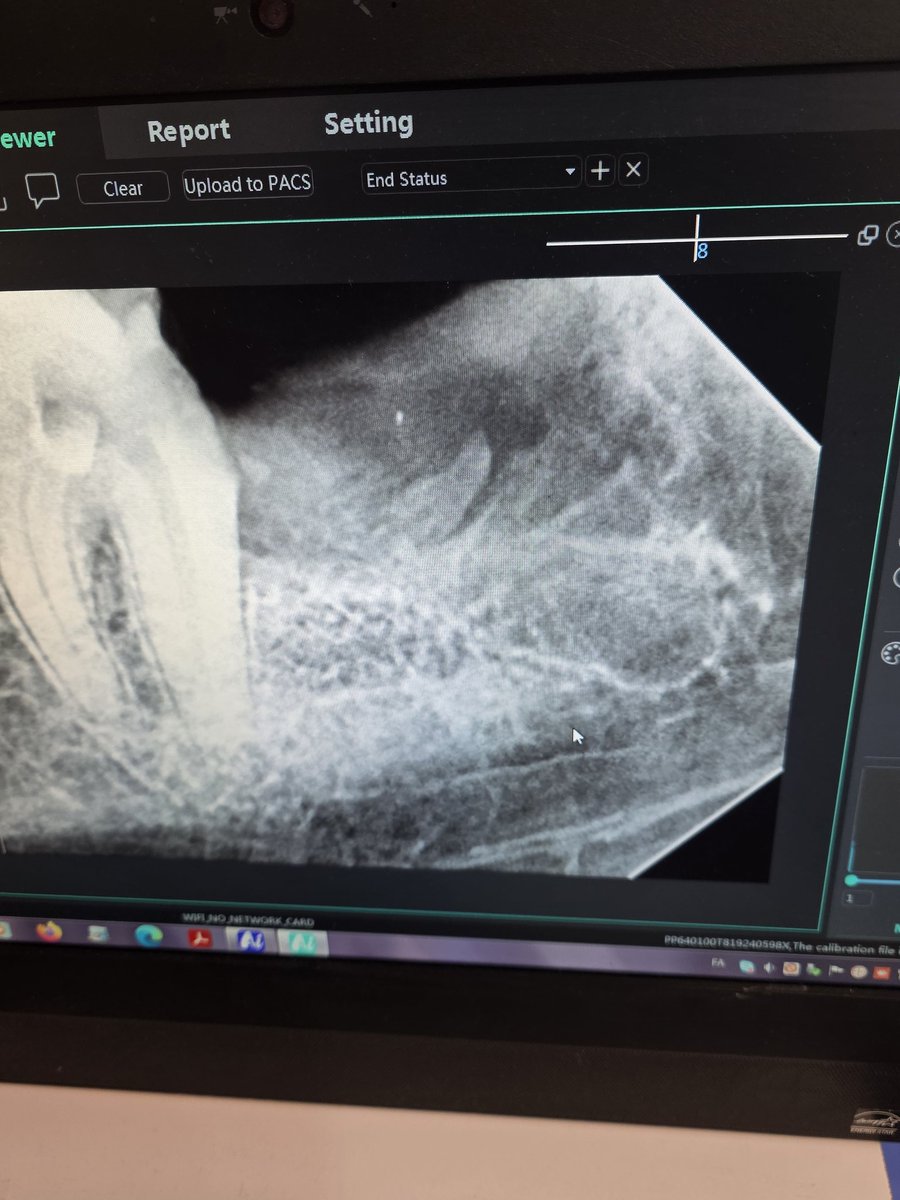

@arrrazz0 متخصص ارتو؟

باز خوبه خودش انجام داد

متخصص کلینیک ما همه بیماراشو دستیارش کار میکنه خودش فقط نگاه میکنه